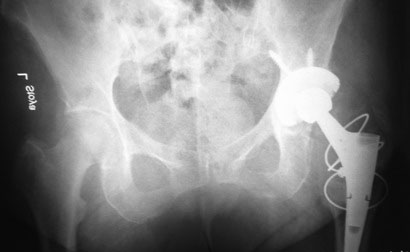

Уважаемые коллеги, помогите определиться!

На консультации женщина 64 лет.

Беспокоят ноющие боли по по передней поверхности правого тазобедренного

сустава около года. В течение последнего месяца боли усилились,

вынуждена пользоваться костылями. Оперирована пять лет назад в Испании.

Документов нет. Послеоперационный рубец, анализы, КТ–  без патологии.

Вопрос: что это за протез и нормально–  ли наличие такого«сочленения»  в

бедренном компоненте или это нарушение стабильности фиксатора?

С уважением, Юрий Алексеевич Булахтин